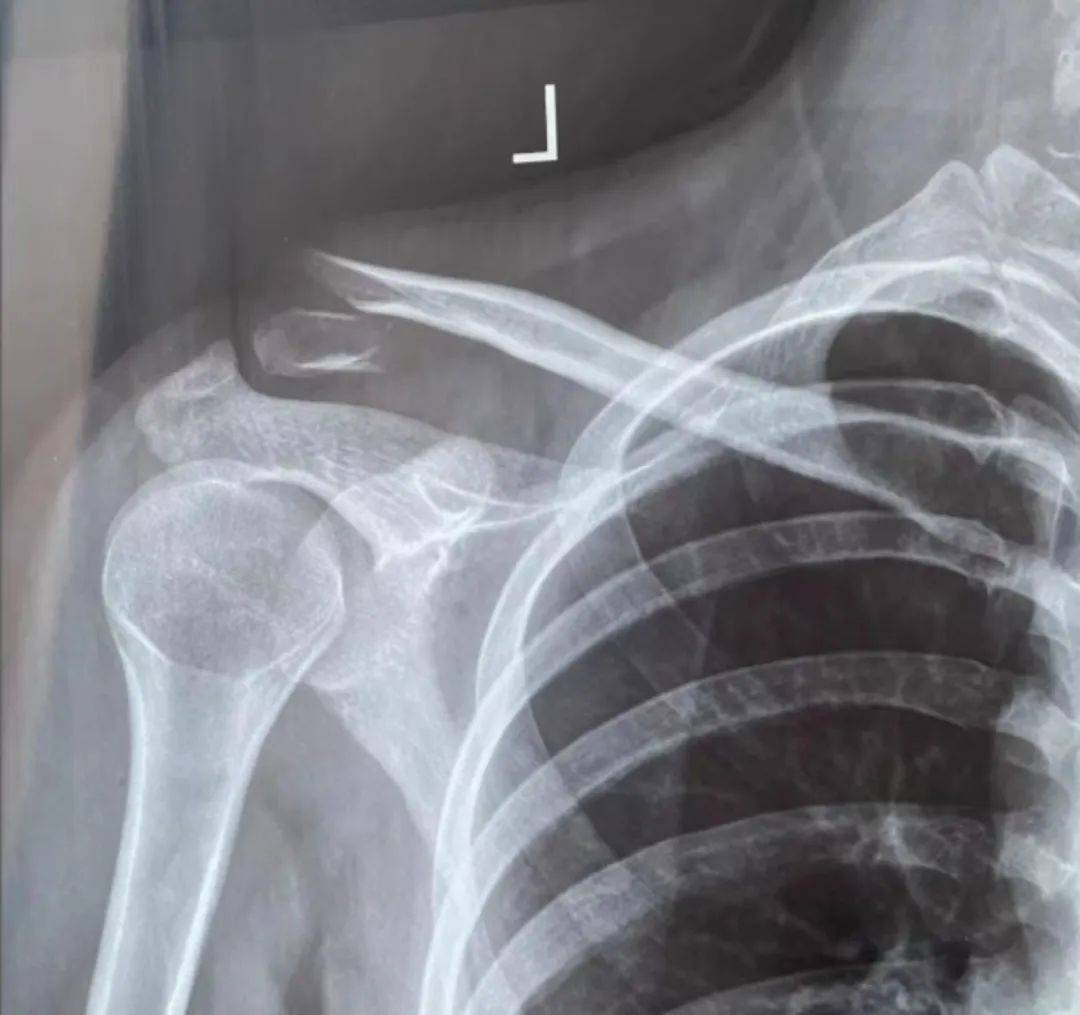

锁骨拍片位置

左侧锁骨远端骨折保守治疗记录